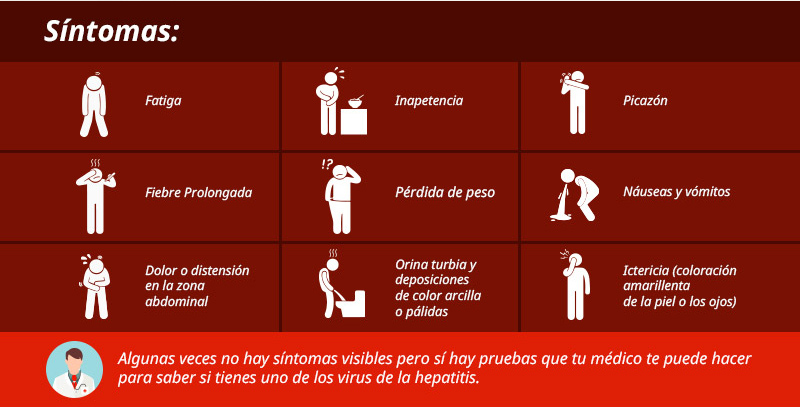

La hepatitis es una enfermedad terrible, no sólo por el profundo deterioro que causa al hígado y que podría provocar la muerte, sino porque se trata de una epidemia silenciosa que muchas veces no presenta síntomas, sino hasta que no hay nada más qué hacer.

Síntomas